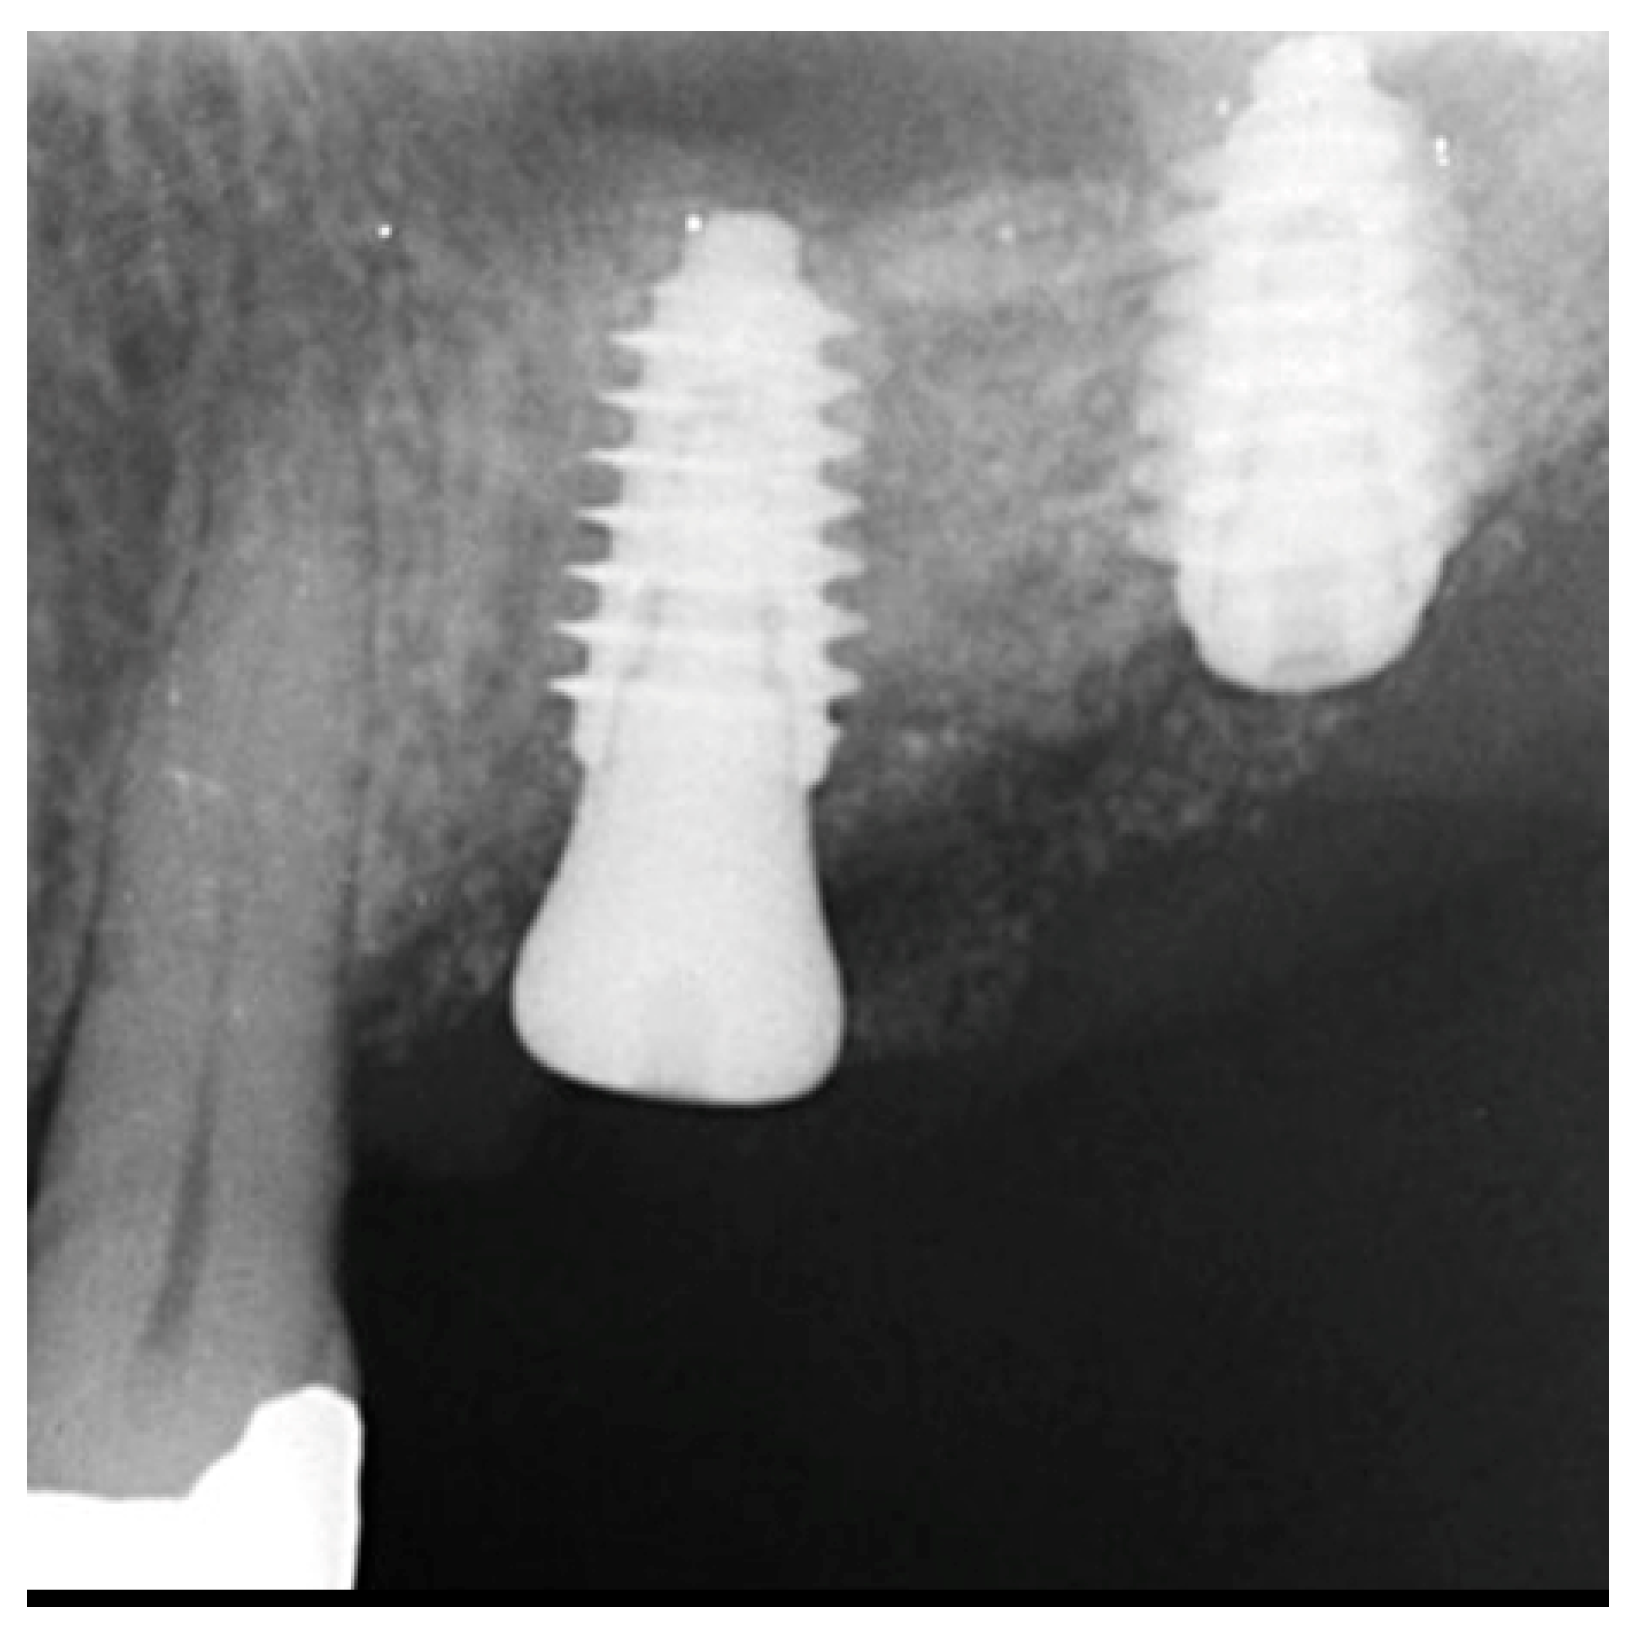

The patient returned at 10 weeks post-2nd-implant placement and a screw-retained restoration was placed on the 1st molar and a radiograph was obtained (Figure 13, left). Impressions were obtained and the restoration on the 2nd molar was placed at a subsequent appointment. Soft tissue was healthy at placement of the restoration on the 2nd molar and no marginal inflammation was noted at either site (Figure 14, left). Soft tissue at the 1-year recall remained healthy and lacking in inflammation (Figure 14, middle). At a 2-year recall, a radiograph was obtained and bone was noted to be stable at both implants (Figure 13, right). Soft tissue at the 2-year recall remained stable and no change in marginal position was noted compared to initial restoration placement (Figure 14, right).

Figure 13.

Radiograph at 10 weeks implant integration at the 2nd molar (left) and two years following restoration of the implant at the 2nd molar showing the improved vertical regeneration between the implants (right).